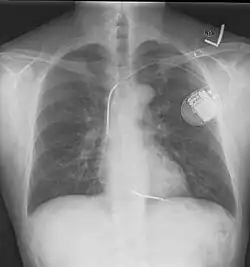

Zdjęcie rentgenowskie klatki piersiowej, radiogram klatki piersiowej, rtg klatki piersiowej (ang. chest X-ray) – badanie radiologiczne polegające na przepuszczeniu przez klatkę piersiową kontrolowanych dawek promieni rentgenowskich, rzutowanych na prostopadłą płaszczyznę z detektorem tych promieni. Rtg klatki piersiowej, tzw. zdjęcie przeglądowe, jest najczęściej wykonywanym badaniem rentgenowskim w medycynie i powinno być pierwszym diagnostycznym badaniem u chorych z objawami choroby płuc. Badanie stanowi około 20% wszystkich badań obrazowych[1]. Jest stosunkowo szybkie i łatwe do wykonania, niedrogie i charakteryzuje się niskim promieniowaniem (około 0,01–0,03 skutecznej dawki mSv dla ekspozycji p-a). Odpowiada to czasowi równoważnemu promieniowaniu tła (promieniowanie jonizujące, które pochodzi z naturalnych źródeł na ziemi, z kosmosu i z wnętrza człowieka) wynoszącemu około 10 dni[2][3][4].

Badanie RTG klatki piersiowej wykonuje się w celu wykrycia lub wykluczenia chorób układu oddechowego, narządów śródpiersia, opłucnej, oraz w ograniczonym zakresie szkieletu kostnego klatki piersiowej i serca. Wyniki badań radiologicznych klatki piersiowej dostarczają wielu wyników, które w dużym stopniu wpływają na decyzje diagnostyczne i terapeutyczne[3].

Badanie to umożliwia także pobieżną ocenę układu sercowo-naczyniowego, pozwala wyciągnąć wnioski na temat wydolności mięśnia sercowego oraz w sposób pośredni wnioskować na temat nasilenia zmian miażdżycowych w organizmie, a także o zmianach związanych z nadciśnieniem tętniczym.

- choroba niedokrwienna serca

- niewydolność serca